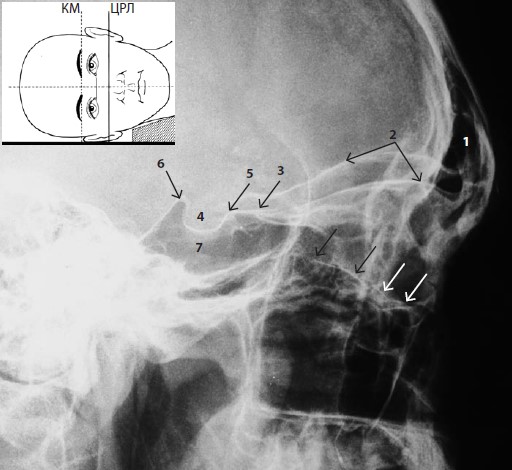

На снимке видны лобные пазухи (1), клиновидное возвышение (3), турецкое седло (4), передний (5) и задний (6) наклоненные отростки клиновидной кости, а также одноименная пазуха (7). Из глазничных структур эта проекция наилучшим образом отображает латеральный край, а также верхнюю стенку (2). Интерпретация состояния дна глазницы (обозначена стрелками) на боковой проекции затруднена из-за его S-образного профиля, элевации по направлению к вершине глазницы, а также суммации изображений обеих глазниц, в результате чего дно создает несколько контуров на снимке.